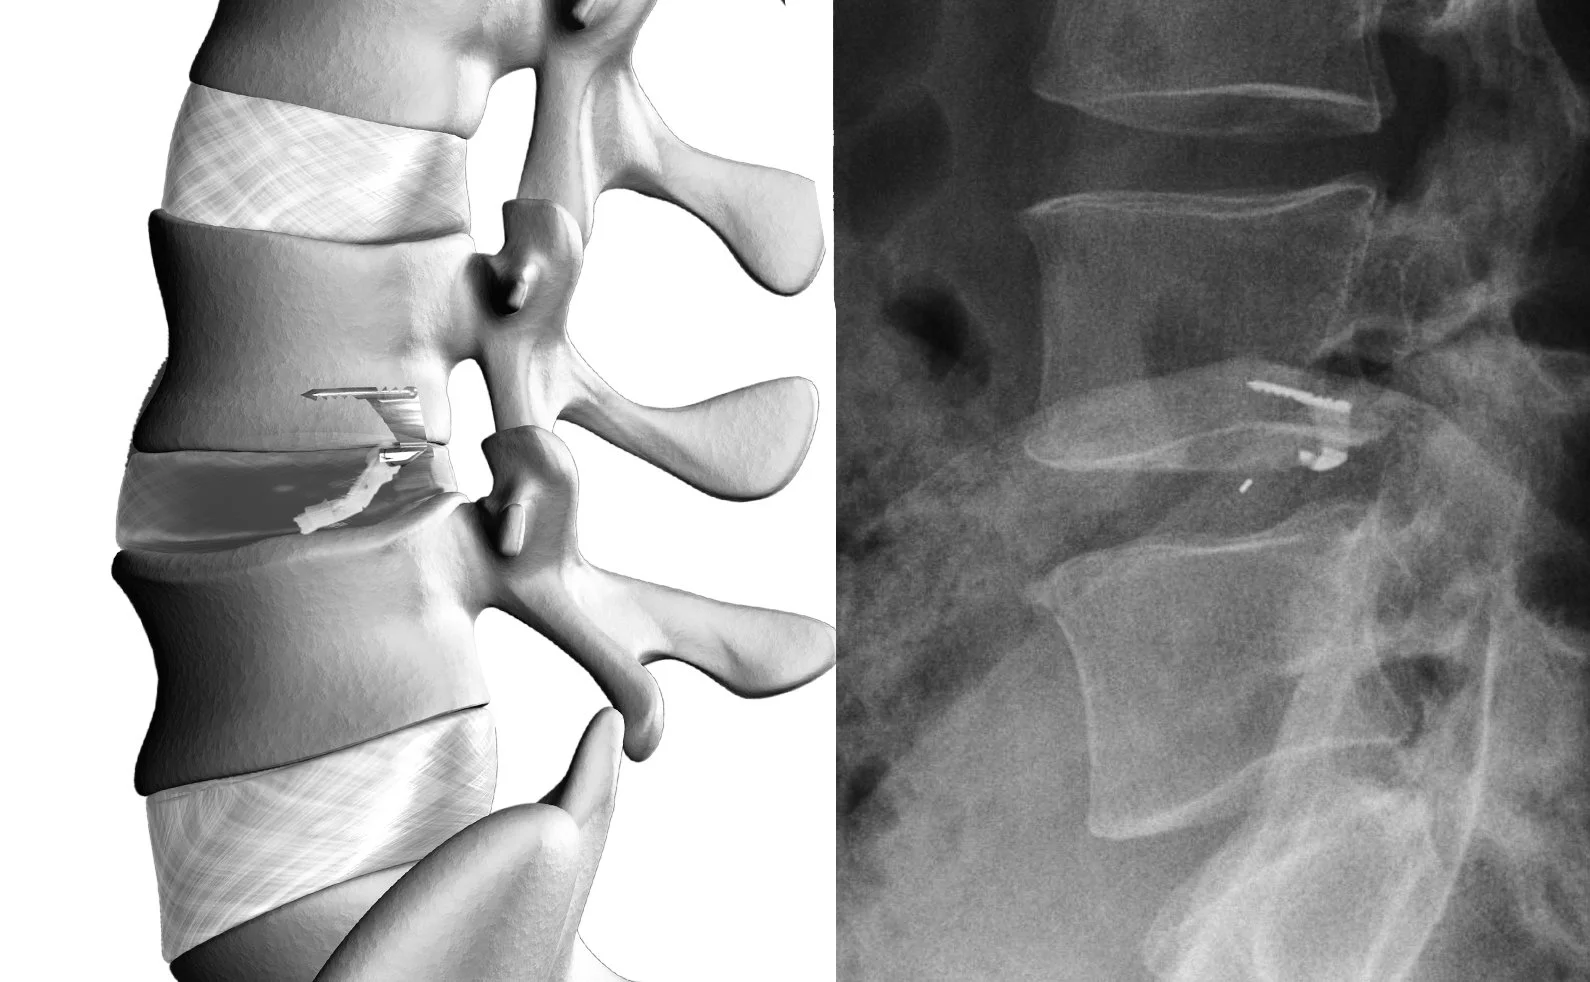

Barricaid® Annular Closure Device

Annular Defect Repair — Reducing Reherniation Risk

When a disc herniates, it tears through the outer disc wall — the annulus fibrosus. After the herniated fragment is removed, this tear (the annular defect) remains open. Patients with a large defect are at significantly higher risk of the remaining disc material re-pushing through that same opening.

When the defect meets clinical criteria, Dr. Katsevman implants the Barricaid® Annular Closure Device — a small, bone-anchored woven implant that permanently seals the defect through the same incision. Clinical studies show Barricaid significantly reduces reherniation risk and reoperation rates compared to discectomy alone.

Not every patient qualifies. Eligibility is evaluated before surgery and confirmed intraoperatively. When indicated, it is one of the most impactful additions available.

Seals the annular defect Reduces reherniation risk Reduces reoperation rates Bone-anchored implant No additional incision